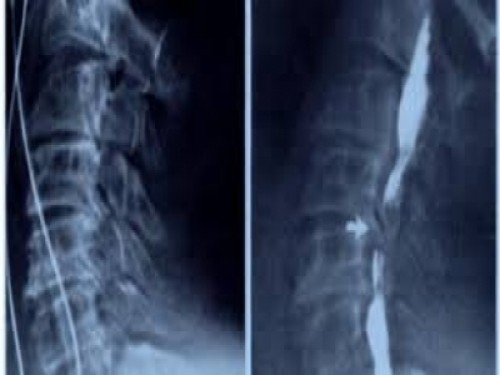

腰椎盤突出

腰椎間盤突出症是常見的腰腿痛疾患,常發於20~50歲的青壯年,它主要因椎間盤勞損變性、纖維環破裂或髓核脫出等,刺激或壓迫脊神經、脊髓等引起的一系列症狀群。